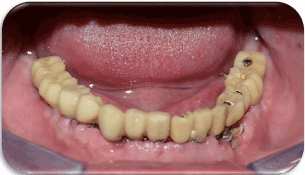

Figure 20. Final Splinted & Non-splinted prostheses Intra-Orally.

Figure 19. Final prosthesis on the cast.